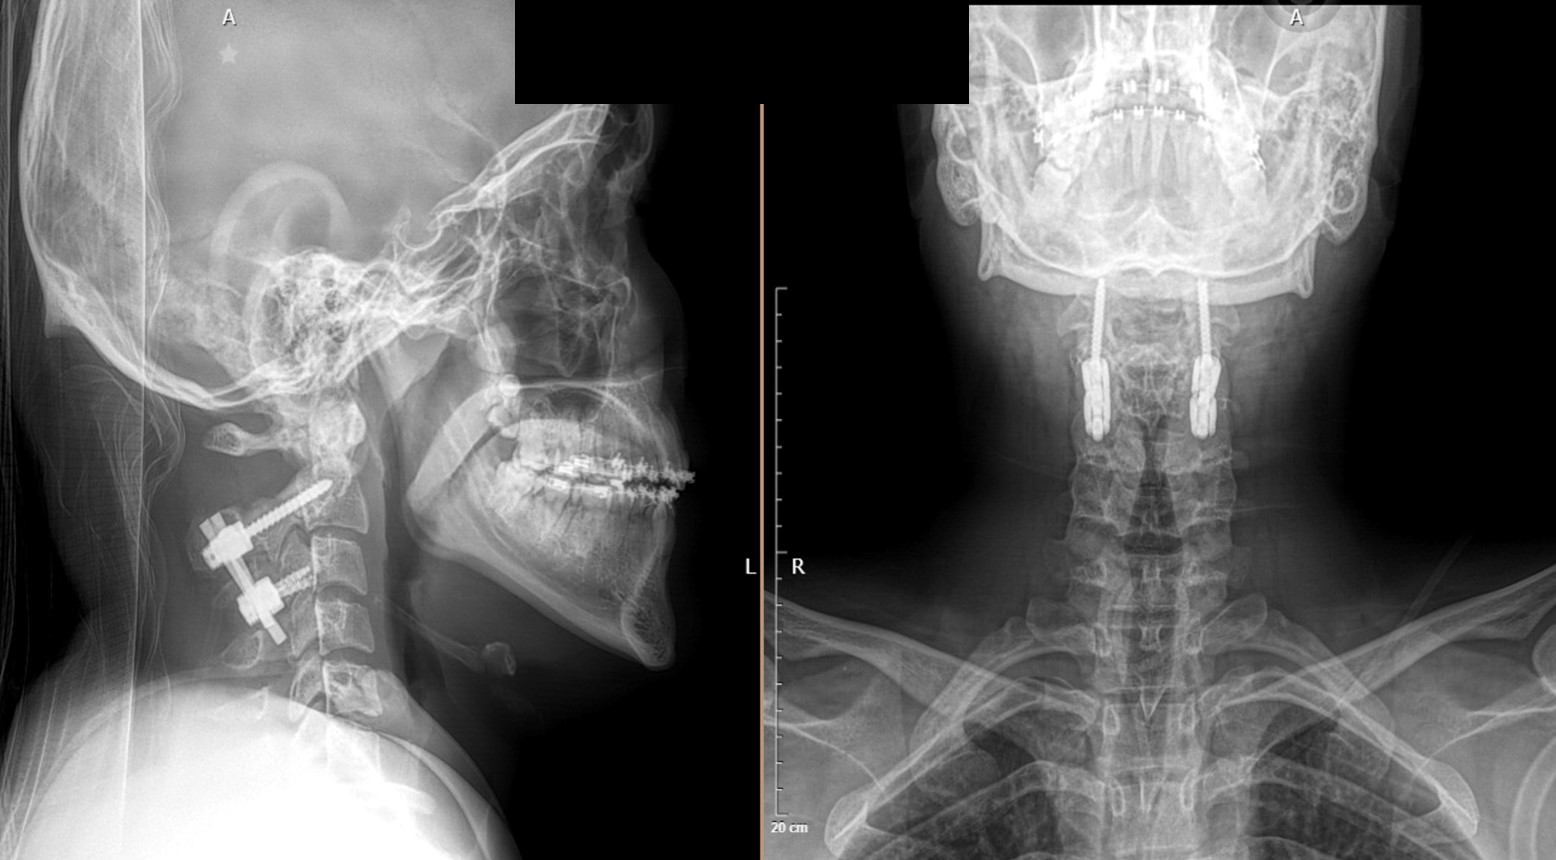

Ejecución en caso real

Paso 5 — Planeación y ejecución en caso real